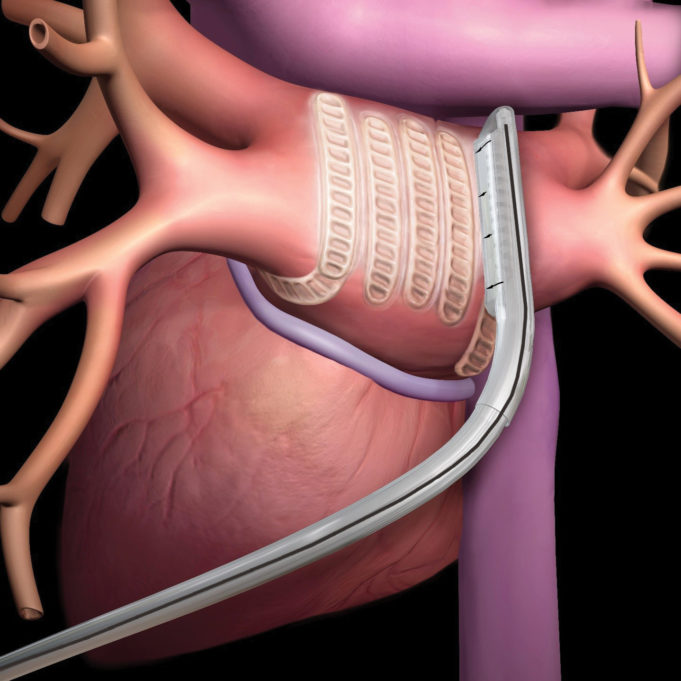

This advertorial has been sponsored by Boston Scientific

Two landmark studies have been published in 2020 following the use of subcutaneous implantable cardioverter defibrillator (S-ICDs) as a primary prevention therapy for sudden cardiac death. Cardiac Rhythm News speaks to the...

Subcutaneous implantable cardioverter defibrillators (S-ICDs) are as protective as transvenous implantable cardioverter-defibrillators (ICDs) in the prevention of sudden cardiac death, but have a better safety profile, the results of a prospective, randomised trial online in a late-breaking trial session...